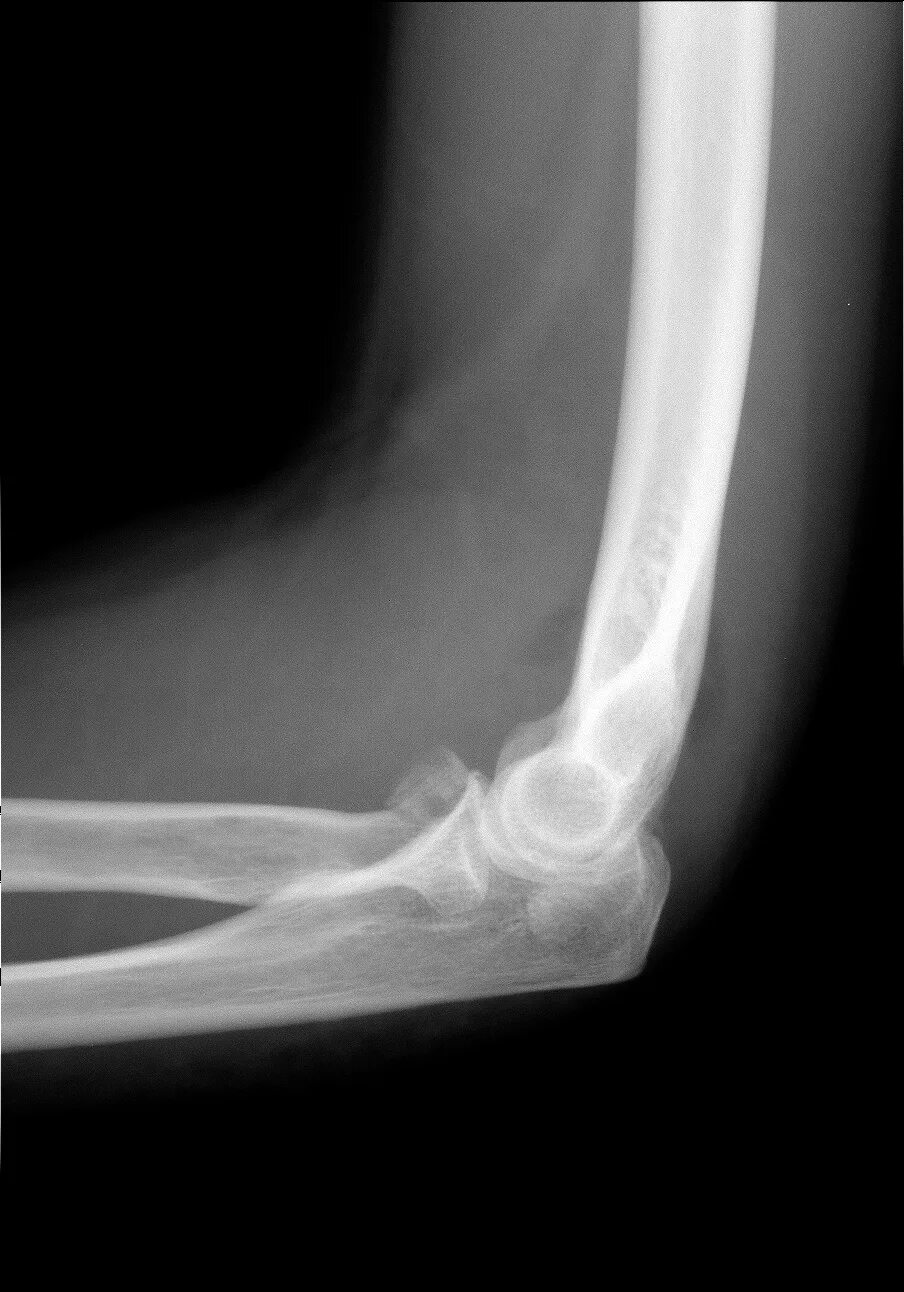

Перелом локтевого отростка травматология. перелом локтевого отростка локтевой кости. локтевой сустав рентген. импрессионный перелом головки лучевой кости.

Локтевой отросток рентген анатомия. перелом локтевого отростка рентген. сесамовидная кость локтевого сустава рентген.

Перелом локтевого отростка рентген. головка локтевой кости рентген. остеохондропатия локтевого отростка.